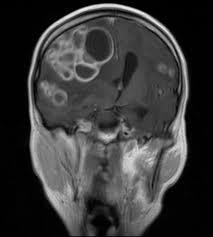

Neuroimagen: realce meningeo basal, hidrocefalia, infartos (vasculitis), tuberculomas

Tuberculomas